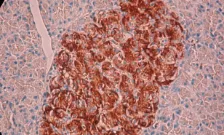

Extracellular matrix and islet function

Prof Peter Jones, Miss Carolin Heller - Native islets in the pancreas possess a complex network of extracellular matrix (ECM) which acts as a structural support and as a reservoir for biologically active molecules which influence islet cell function. Islet ECM is largely destroyed during islet isolation with deleterious effects on islet survival and function. We have recently shown that ECM laid down by stromal cells grown in 2D monolayers is beneficial for islet survival and function, so we are now exploring ways to replace islet ECM using 3D co-cultures of islets with mesenchymal stromal cells and islet stellate cells.